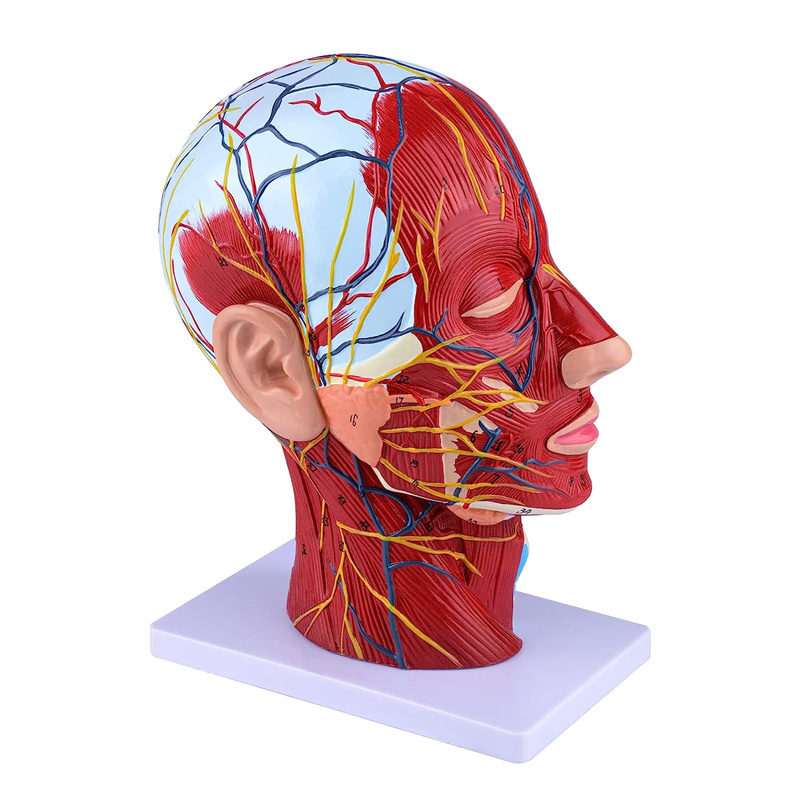

| פֿעיִקייטן | דער מאָדעל ווייזט די היגע מאָרפאַלאַדזשי פון די ינער און ויסווייניקסט זייטן פון די מידיאַן סאַגיטטאַל אָפּטיילונג פון די קאָפּ און האַלדז, און די סטראַקטשערז פון בלוט כלים און נערוועס און עס זענען 84 פּאַרץ ינדאַקייטינג וואונדער אין גאַנץ. |

【Superficial Neurovascular Muscle Model】Highly detailed, numbers marked, detachable ear, deepen the understanding of the superficial muscles, vessels, nerves and the internal structures of the head & neck. רויט-אַרטעריע, בלוי-אָדער, געל-נערוו.

【פֿעיִקייטן】 עס געוויזן די אויבנאויפיקער מאַסאַלז פון די יקספּאָוזד פּנים; די אויבנאויפיקער בלוט כלים & נערוועס פון די פּנים & סקאַלפּ; די ינער סטראַקטשערז פון פּאַראָטיד דריז & אויבערשטער רעספּעראַטאָרי שעטעך; די סאַגיטטאַל קרייַז-אָפּטיילונג סטרוקטור פון די סערוואַקאַל רוקנביין.

דער מאָדעל ווייַזן דעטאַילס פון די רעכט קאָפּ האַלדז און מיטן סאַגיטטאַל אָפּטיילונג פון דער מענטש. אַרייַנגערעכנט די אויבנאויפיקער

מאַסאַלז פון די יקספּאָוזד פּנים; די אויבנאויפיקער בלוט כלים און נערוועס פון די פּנים און סקאַלפּ; די ינער סטראַקטשערז

פון פּאַראָטיל דריז און אויבערשטער רעספּעראַטאָרי שעטעך; די סאַגיטטאַל קרייַז-אָפּטיילונג סטרוקטור פון די סערוואַקאַל רוקנביין.

דער מאָדעל געוויזן די היגע מאָרפאַלאַדזשי פון די מעדיאַל און לאַטעראַל סאַגיטטאַל סעקשאַנז פון די קאָפּ און האַלדז און די וואַסקיאַלער און נערוו סטראַקטשערז, מיט אַ גאַנץ פון 100 פּלאַץ ינדאַקייטערז.

דער מאָדעל איז נאַטירלעך גרויס קאָפּ און האַלדז אויבנאויפיקער נעוראָוואַסקולאַר מוסקל מאָדעל, 1 קאָמפּאָנענט, ווייַזונג די דעטאַילס פון די מענטשלעך רעכט קאָפּ און מעדיאַן סאַגיטטאַלע אָפּטיילונג, אַרייַנגערעכנט די יקספּאָוזד בעשאָלעם און די מעדיאַל סטרוקטור פון די פּאַראָטיד דריז און אויבערשטער רעספּעראַטאָרי שעטעך, און די סאַגיטטאַל אָפּטיילונג סטרוקטור פון די סערוואַקאַל רוקנביין